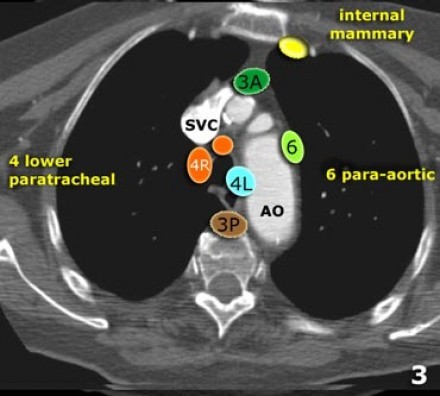

3. Linfonodos Prevasculares e Prevertebrais

Linfonodos estação 3 não estão adjacentes à traqueia como os linfonodos estádio

Eles podem ser:

3A - anteriores aos vasos

3P - posteriormente ao esôfago, prevertebrais

Linfonodos estadio 3 não são acessíveis à mediastinoscopia.

Linfonodos 3P podem ser acessados com ultrassonografia endoscópica.